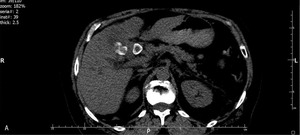

U chorej wykonano badanie TK z fazą pokontrastową (ryc. 2A-C).

Spośród wymienionych wyżej jest to metoda optymalna ze względu na koszt i dostępność oraz wartość diagnostyczną. Badanie wykluczyło obecność złogu w jamie otrzewnej, potwierdzając jednocześnie występowanie zwapnień pozapalnych w dnie pęcherzyka żółciowego i rozległego nacieku w sąsiadującym miąższu wątroby. Obraz zmiany i charakter wzmocnienia w fazie tętniczej (ryc. 2C) nie pozwalają na różnicowanie zapalenia i nacieku raka pęcherzyka żółciowego.